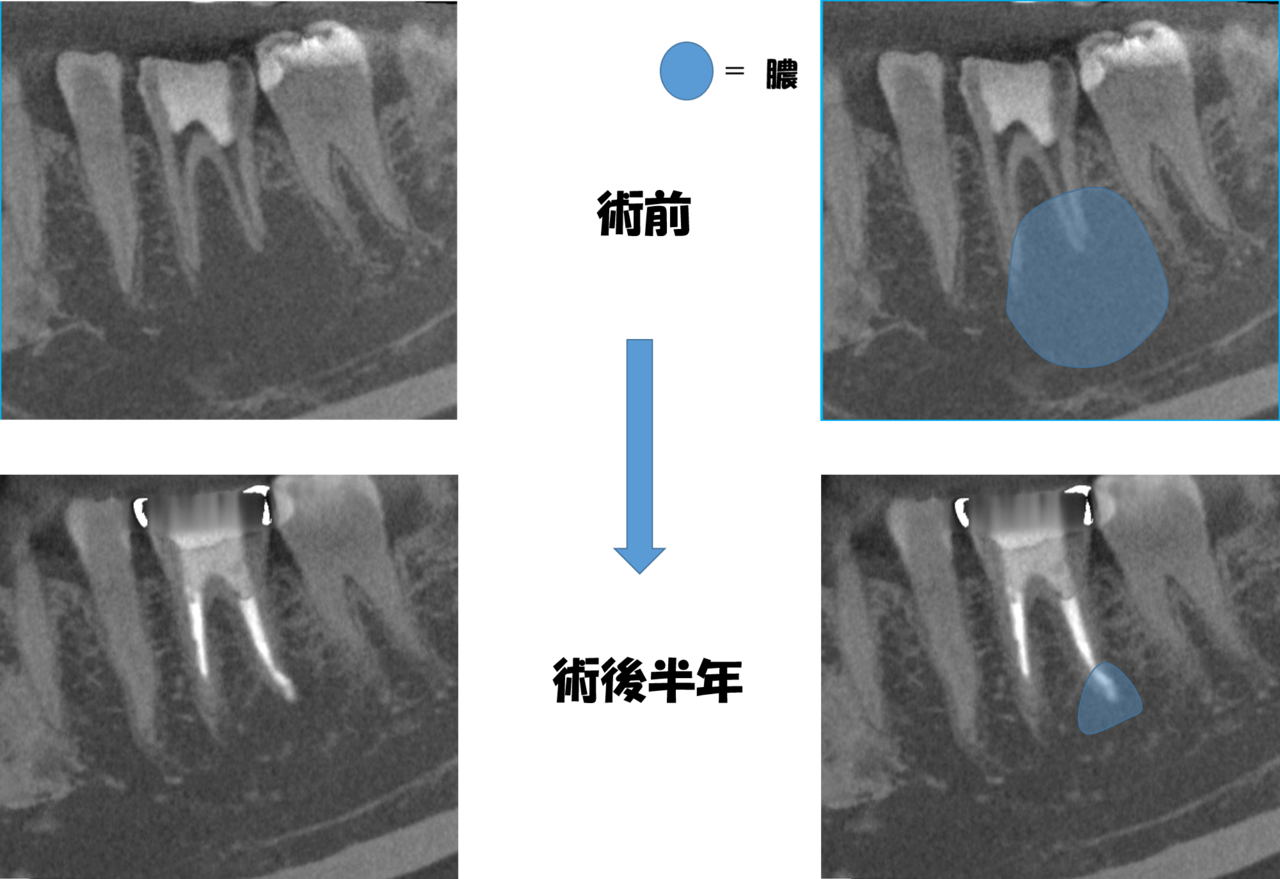

上は左右同じ写真です。右図は根尖病変(膿)の範囲を示したもの。

CTを撮影すると、病変の範囲がよくわかります。

下歯槽神経に近接する大きな病変。大きくても治るものは治ります。

左右同じ写真です。

術前と同じ部分CTを撮影したところ、

病変はだいぶ縮小していました。

膿が止まっても病変の大きさが変わらない(治っていない)ケースもありますから、確認するまで心配でした。

完全に病変が消失するまで、もう少し様子をみたいと思いますが、外科処置はなんとか避けられそうです。